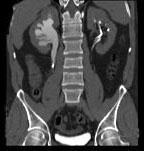

问题 男,36岁,反复发作的右侧腰背部疼痛伴血尿1年余,CT如图所示,下列说法正确的是 ( )

选项 A、右输尿管结石 B、右输尿管上段钙化 C、右输尿管上段扩张 D、右输尿管内可见沿输尿管走行的高密度影 E、右侧肾盂肾盏扩张

答案 ACDE